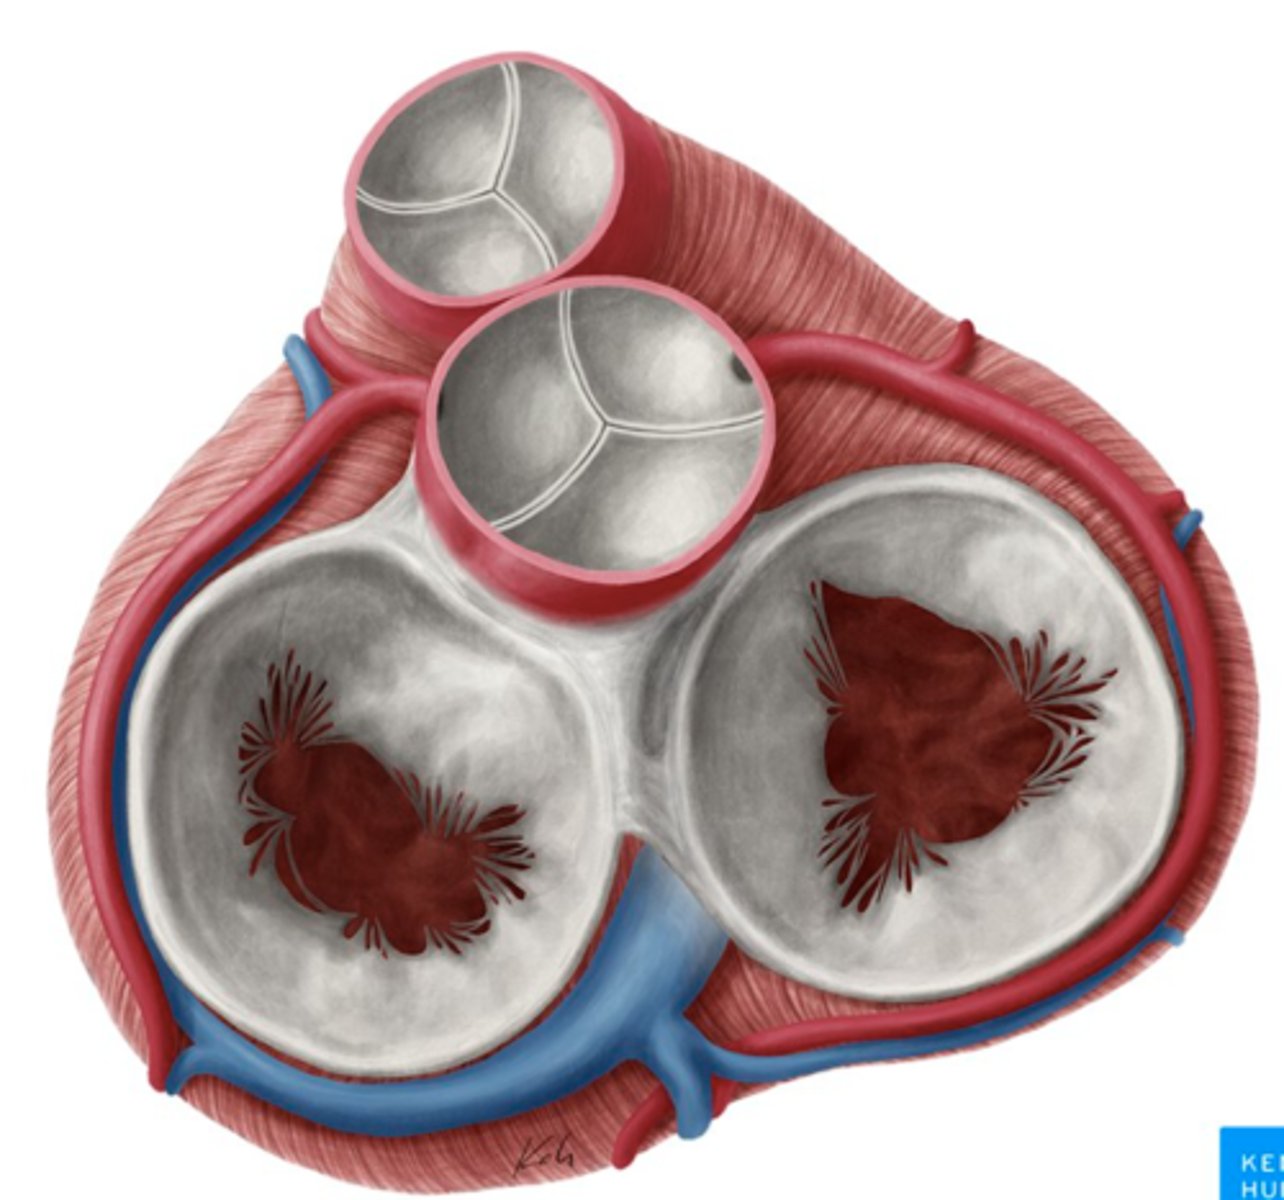

AXIAL VIEW OF THE HEART

What are the 3 cusps of the tricuspid valve?

Anterior

Posterior

Septal

What are the positions of the pulmonary valve cusps?

Anterior

Right

Left

What is the valve in the AV left canal?

. Mitral valve

2 cusps (anterior and posterior) and 2 associated papillary muscles

What are the 3 parts of the aortic valve?

3 semilunar cusps

posterior

right

left

What are the four valves in the heart?

Tricuspid

Mitral or bicuspid

Pulmonary

Aortic

What are other functions of the rings in the cardiac skeleton?

maintain the shape of the openings between the heart's chambers

insertion site for the cusps of the valves and muscular heart tissue.

What are the components of the cardiac skeleton?

. pulmonary ring,

. aortic ring

. AV rings

RINGS ARE IN THE SAME PLANE AROUND THE VALVES